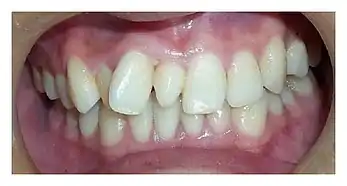

Un diente supernumerario no tiene antecesor ni reemplazante. Generalmente tiene una sola raíz y puede semejarse estrechamente a los dientes del grupo al que pertenecen, cuando esto ocurre se le denominan suplementarios. Se ha sugerido que los supernumerarios se desarrollan a partir de un tercer germen dental, que surge de la lámina cercana al germen dental permanente o posiblemente de la división de este.

Generalmente presentan una sola raíz, tienen un tamaño muy pequeño y a veces presentan aplasia de los lóbulos mesiales y distales con forma de cono (conoidismo), aunque muchas veces los cuartos molares pueden tener una morfología normal.[5]